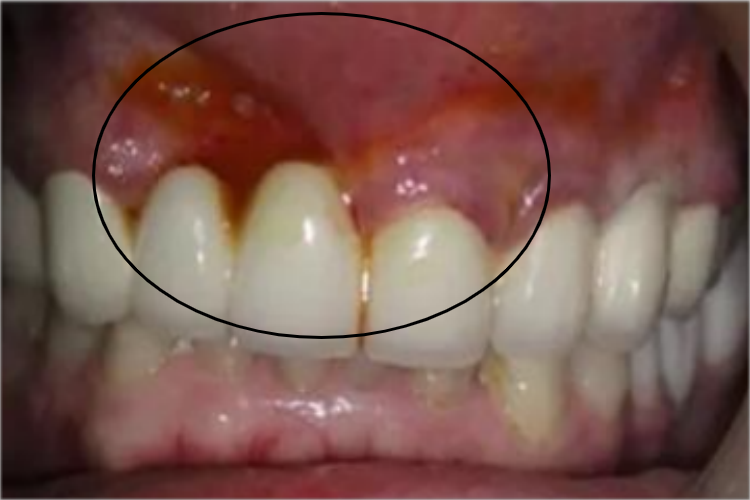

急性浆液性根尖周炎可以表现为牙龈萎缩,暴露出较多的牙根,局部黏膜肿胀,同时可伴有渗液,渗液为血性的浆液,从牙龈渗出,患者进行咬合等动作时可有疼痛症状出现。

急性浆液性根尖周炎多由感染的牙髓通过根尖孔刺激根尖周组织而引起。此外,创伤、根管治疗时药物刺激等因素均可造成本病的发生。

急性浆液性根尖周炎首先需要遵医嘱消炎止痛,待症状缓解后采用根管治疗或牙髓塑化治疗。可对患牙进行开髓、拔髓,并用消毒剂(如次氯酸钠)浸泡、冲洗根管,并对根尖周组织的炎症渗出液进行引流,缓解局部压力。